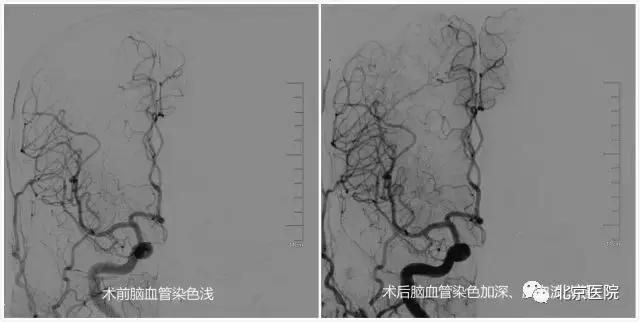

针对颈动脉狭窄,早在上世纪90年代,北京医院神经外科刘树山主任就开展了颈动脉内膜剥脱术;2002年,在国内最早报道了采用脑保护装置辅助进行颈动脉狭窄支架成形术。神经外科还与神经内科、放射科、超声医学科、核医学科等兄弟科室开展长期合作,围绕颈动脉狭窄患者的认知功能、脑血流灌注、颈动脉斑块稳定性等热点和难点问题,进行了深入的临床和基础研究;先后承担了原国家卫生部临床学科重点项目、首发基金项目、北京医院“121项目”等多项科研课题;发表相关学术论文30余篇;主办了大型脑血管病研讨会10余次。值得一提的是,作为国家老年医学中心,北京医院接诊的颈动脉狭窄患者一直以老年、高龄患者居多,仅在2016年,就治疗了老年颈动脉狭窄患者74例(占总数70%多),无一例出现严重手术并发症。